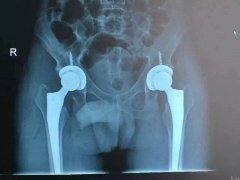

近日,我院骨科成功為一名老年男性患者實(shí)施雙側(cè)股骨頭無菌性壞死人工髖關(guān)節(jié)小切口DA……